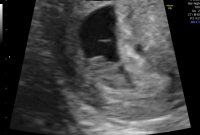

6+0, målene stemte med hvor langt jeg var på vei og vi fikk se et blinkende hjerte![]()